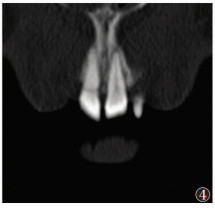

2 结果28例共49颗牙齿根折(图 1),其中单颗牙根折18例(64.3%),多颗牙根折10例(35.7%);中切牙根折39颗(79.6%),侧切牙根折10颗(20.4%);8例合并冠折;9例合并邻近牙槽突骨折;10例合并邻牙损伤,其中6例为牙齿缺如,4例为冠折(图 2,3)。49颗根折牙齿中,骨折线位于根颈1/3处12颗(24.5%),根中1/3处6颗(12.2%),根尖1/3处31颗(63.3%),以根尖1/3处最常见(图 4,5)。

| 图 4 男,23岁,21牙根颈1/3处根折 |